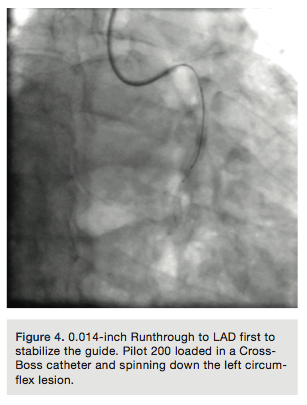

A Pilot 200 wire (Abbott Vascular) was loaded in a CrossBoss catheter (Boston Scientific) and advanced into the circumflex artery. The CrossBoss was slowly advanced, using the Pilot wire to redirect the device to remain as close to the lumen as possible. Once past the total obstruction, the Pilot 200 wire was used to re-enter the distal circumflex (Figures 3-4). A balloon dilation with a 1.5 mm x 20 mm long balloon was performed at 12 atmospheres (atm) followed by a 2.5 mm x 20mm balloon at 12 atm. A Runthrough wire (Terumo) was placed in the first marginal and stenting of the circumflex was performed using a 2.5 mm x 38 mm Promus Premier stent (Boston Scientific) overlapped with a 3.0 mm x 24 mm Promus Premier stent. High-pressure inflation in the entire stented segment was performed using a 3.0 mm balloon. The segment proximal to the first obtuse marginal was dilated to high pressure using a 3.25 mm balloon (Figures 5-7). A good angiographic result was seen (Figure 8).